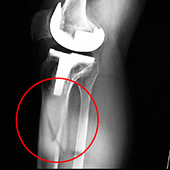

Periprosthetic Knee Fractures

Knee replacement, also called knee arthroplasty, is a surgical procedure in which the worn-out or damaged surfaces of the knee joint are removed and replaced with artificial implants. Any resulting fractures or breaks in the bone around the implant are called periprosthetic knee fractures. These fractures may occur during surgery (intraoperative) or after surgery (postoperative), and usually involve the patella, tibia or the femur (kneecap, shinbone, and thighbone). Women are at higher risk than men.